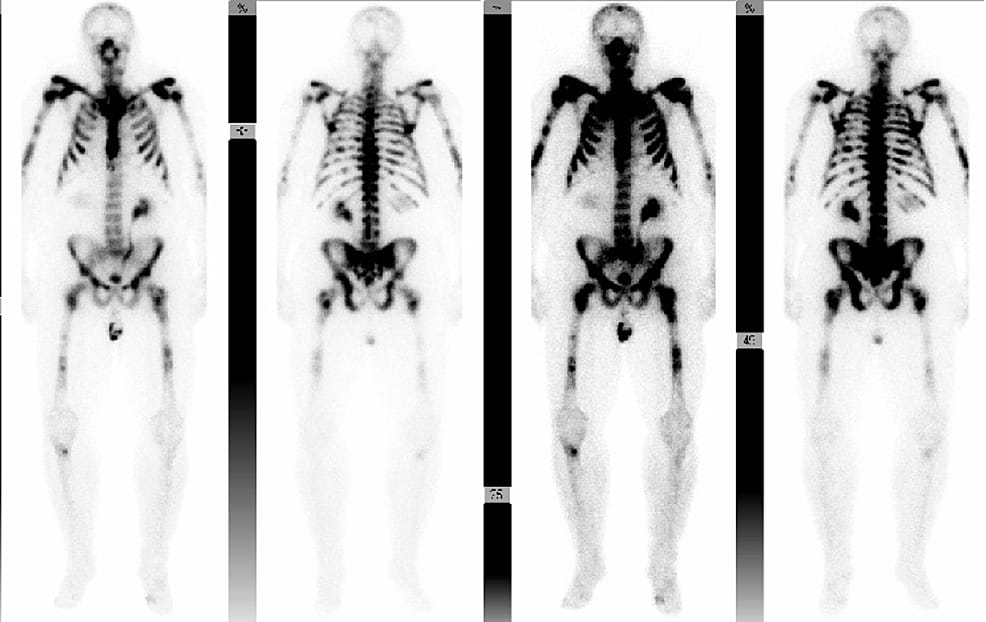

This paper discusses an assumption that osteoporosis is not a concern for younger men. By following men diagnosed with metastatic PCa before age 55, the authors show how misleading that assumption can be once androgen deprivation therapy (ADT) enters the picture. Using routine CT scans already obtained for cancer surveillance, they tracked changes in vertebral bone density over time while carefully excluding areas affected by bone metastases.

What they found was striking. Bone density fell steadily over the course of ADT treatment, dropping by roughly 14% on average, with nearly one in three men meeting imaging criteria for osteoporosis by their last scan. This decline occurred despite a mean age just over 51 at diagnosis and long survival times, highlighting that bone loss is not just a late-life problem in this setting.

The clinical consequences were not theoretical. More than 40% of patients experienced a fracture, and fracture risk was highest among those whose imaging showed osteoporosis. Although guidelines recommend calcium and vitamin D for all men on ADT, only about half received both.